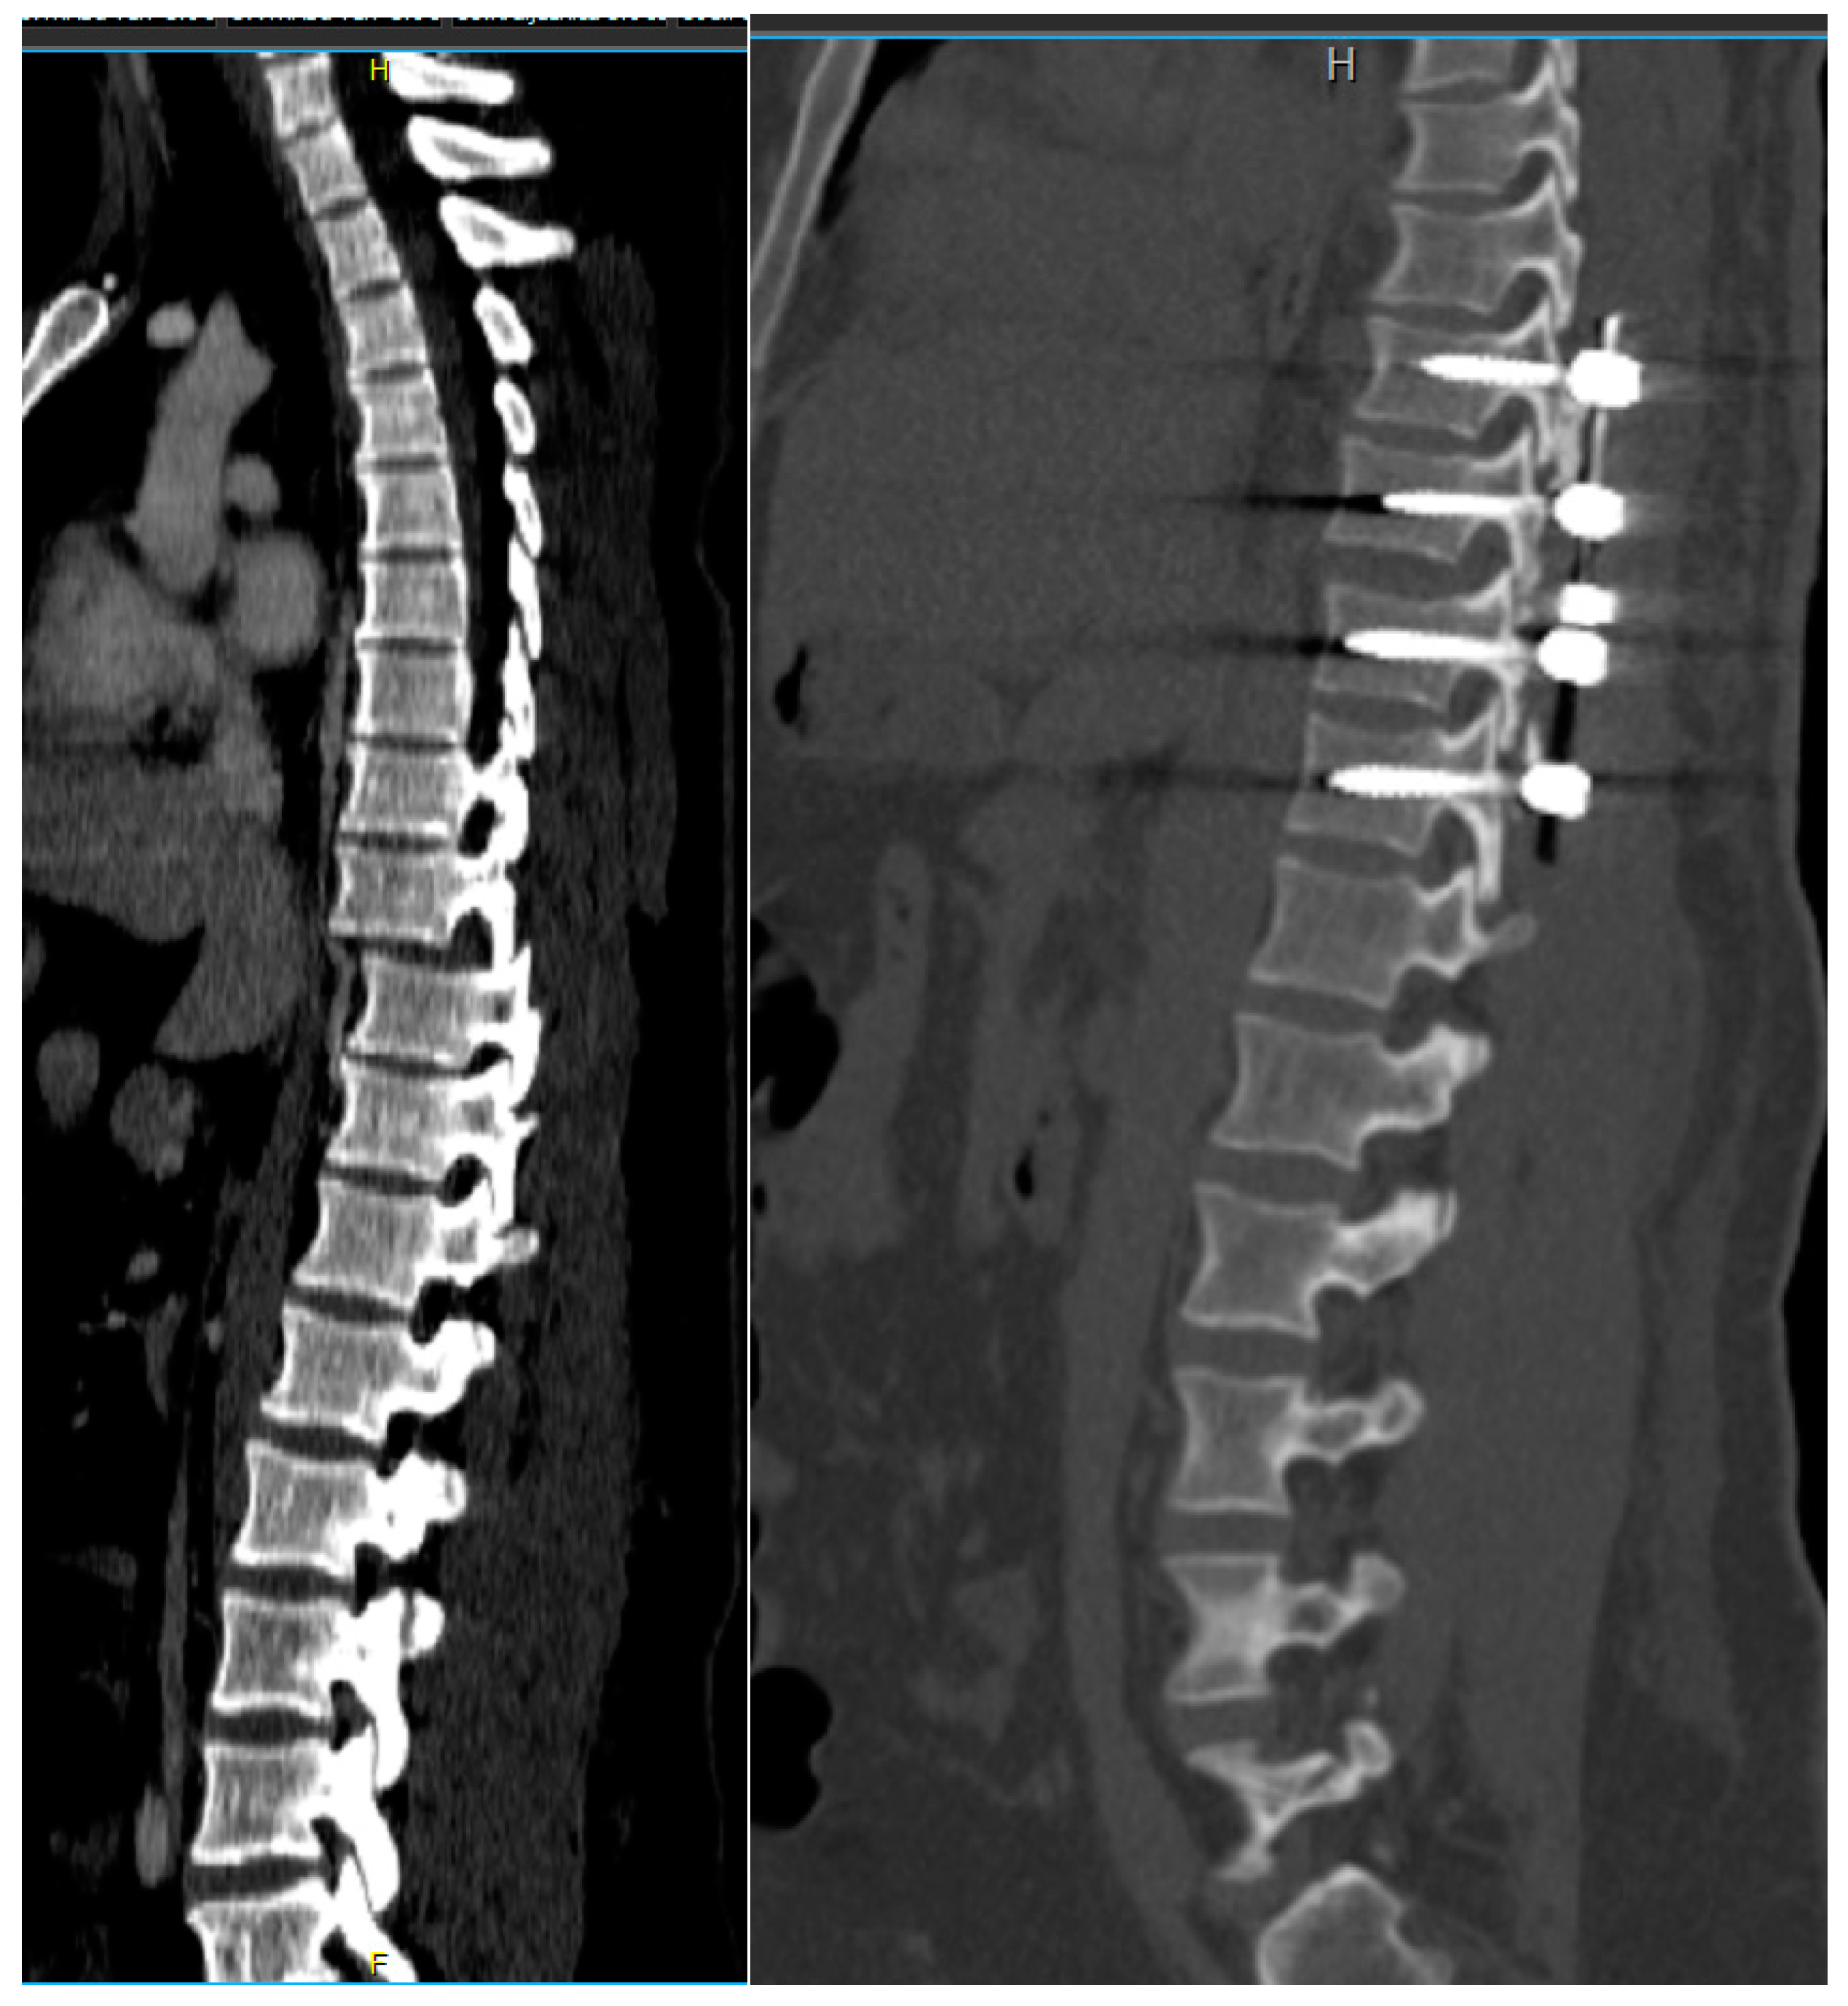

Figure 2.

Preoperative CT scan showing a bilateral locked facet fracture–dislocation of the Th11–Th12 levels. The tips of the superior facet joints were also fractured indicating the high violence of the injury causing bilateral locked facet dislocation.